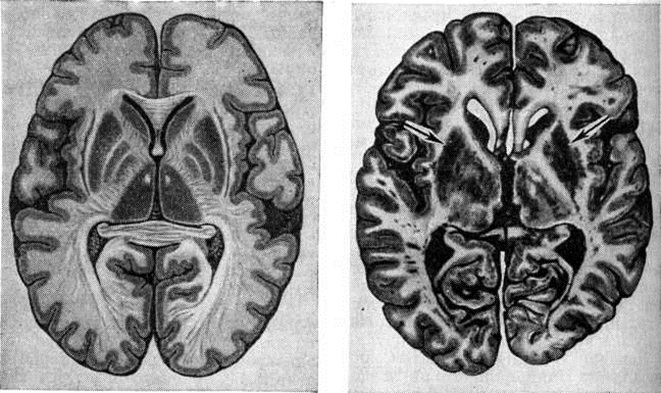

Рис. 1.

Горизонтальный (на уровне спайки свода) срез головного мозга; на рисунке справа срез мозга больного, умершего от гепато-церебральной дистрофии с двусторонним сморщиванием (дистрофией) чечевичных ядер (указано стрелкой); на рисунке слева срез нормального мозга.